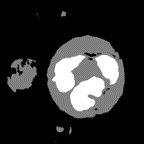

Figure 8: Attention map in Top-Down PDA-Module

4.3.4 Visualization of Top-Down PDA-Module

Visualization results of the attention map in Top-Down PDA Module are shown in Figure 8. In the first epoch, the probability of the correct class is low at almost pixels. In the second epoch, the probability of the correct class is low for the cell nucleus and red blood cells in the background. As training advances, we can see that the probability of the correct class is low at the edges and in small regions. This indicates that these pixels are more difficult to recognize than the other pixels. Since the pixels with relatively low probability for the correct class contain a lot of information for identifying the object’s outline, they are considered to be of relatively high importance during training.